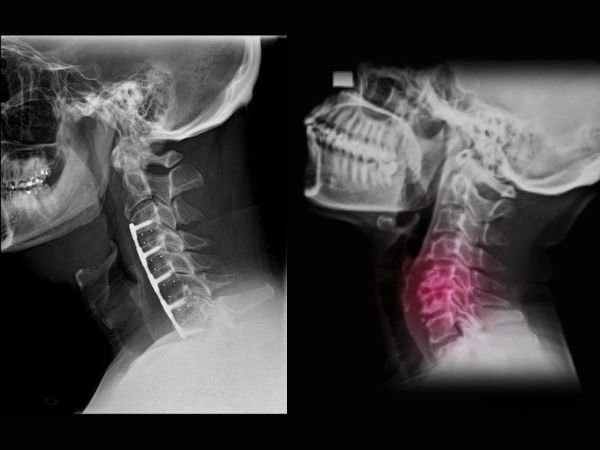

One of the most popular spine procedures to relieve pressure on the spinal cord or nerve roots in the neck is cervical discectomy. It is intended to treat degenerative disc disease, myelopathy, cervical radiculopathy, and cervical disc herniation that has not responded to conservative treatment.

During a cervical discectomy, a damaged or herniated disc in the cervical spine (neck region) may be removed entirely or in part by the surgeon. The goal is to take pressure off the spinal cord and nerves to relieve pain, numbness, tingling, and weakness in the neck, arms, or hands.

- ACDF, or anterior cervical discectomy and fusion

- Most frequently carried out.

- The surgeon uses the neck crease to approach the spine from the front.

- The damaged disc is taken out.

- A cage or spacer is put in.

- The spine is stabilised via fusion using a plate and screws.